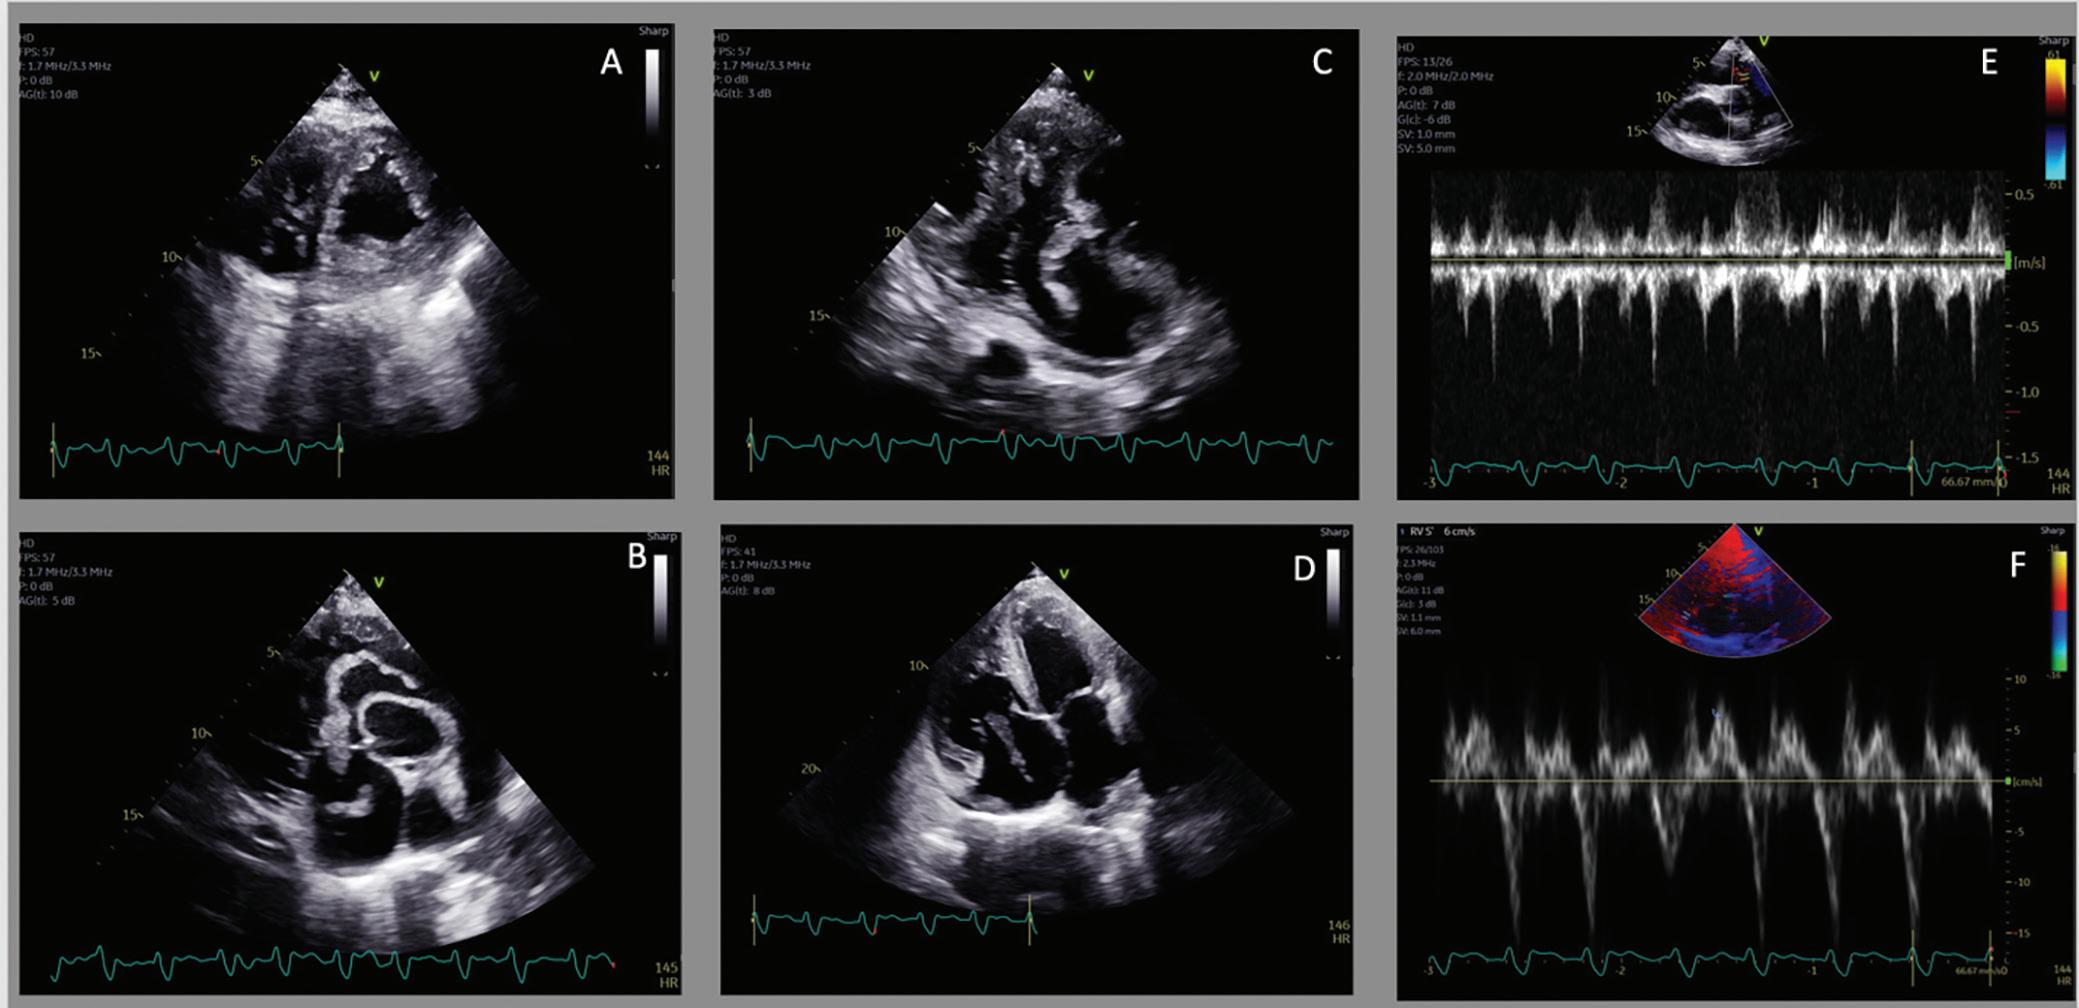

Case: A 68-year-old man with sarcoidosis presented with dyspnea and lower extremity edema. His prior cardiac workup was notable for transthoracic echocardiogram (TTE) with left ventricular (LV) dysfunction, coronary angiogram with normal coronaries, cardiac MRI with severe biventricular dysfunction as well as subepicardial to near transmural scar of the basal to mid inferolateral walls, and pulmonary function test with severe obstructive ventilatory impairment and positive bronchodilator response.

Upon presentation, he was tachycardic, tachypneic, hypoxic, and normotensive. His laboratory studies revealed leukocytosis 23 x 109/l, creatinine 1.52 mg/dl, venous lactic acid 3.5 mmol/l, pro B-type natriuretic

peptide 34,807 pg/ml and negative troponin. Chest radiography was notable for a right upper lobe wedge-like opacity and right pleural effusion. Electrocardiogram revealed rapid atrial flutter. Supplemental oxygen was started and furosemide was administered. Digoxin load was given without improvement. A TTE showed a severely decreased LV function, dilated right ventricle (RV) with reduced contractility and thrombus in transit extending from the right atrium (RA) to RV (Figure 1). Heparin was started and the patient was transferred for consideration of advanced therapies.

Figure 1

A: PSAX with RV pressure overload; B: PSAX with thrombus in transit from RA through RV and into RVOT; C: RV in-flow with thrombus in transit; D: RV in-flow with thrombus in transit and RV enlargement; E: Pulsed Wave Doppler RVOT. F: S’ of RV showing reduced RV function. PSAX = parasternal short axis view; RA = right atrium; RV = right ventricle; RVOT = right ventricular outflow tract.

cardiopulmonary reserve and tenuous hemodynamics; he underwent urgent percutaneous mechanical thrombectomy with removal of thrombus in the RA, RV, and main pulmonary arteries. There was a distal residual clot (Figure 2). Hemodynamics showed a CI of 2 l/m2 and severe pulmonary hypertension, with improvement to 2.7 l/m2 following intervention, though during the procedure the patient required intubation due to delirium. His postoperative period was notable for RV cardiogenic shock as well as auto-positive end-expiratory pressure due to bronchospasm. Following ventilator adjustments, bronchodilators, corticosteroids, inhaled nitric oxide and milrinone, there was stabilization. Acute and extensive clot burden was evident in bilateral lower extremities on Doppler ultrasound. His course was further complicated by oliguric acute kidney injury and volume overload despite diuresis, requiring continuous veno-venous hemofiltration (CVVH) as well as difficult-to-control atrial tachycardia with variable block requiring direct current cardioversion. Thereafter, stabilization of the patient’s